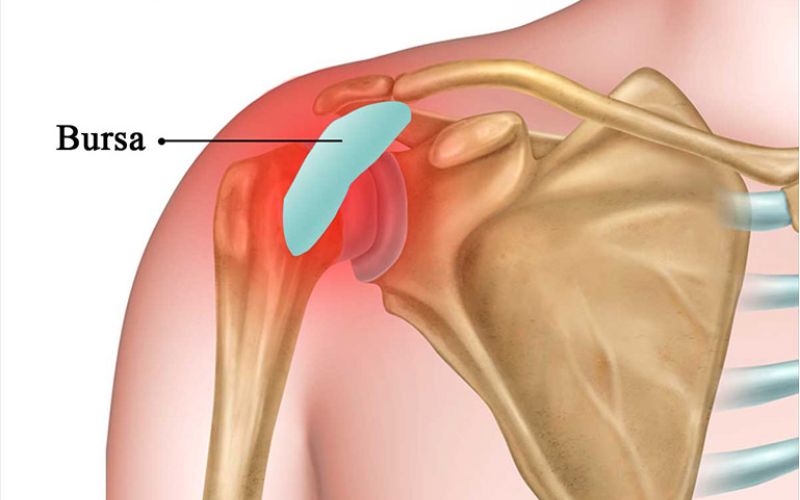

Viêm bao dịch khớp vai trái

Bao dịch khớp vai giúp giảm ma sát giữa gân và xương khi cử động. Khi bao dịch bị viêm, vai dễ đau khi bạn ngủ nghiêng về một bên. Áp lực trong lúc ngủ khiến bao dịch căng và gây đau bả vai trái khi dậy. Người vận động vai quá sức hoặc chịu va đập nhẹ dễ gặp tình trạng này. Cơn đau thường tăng khi bạn giơ tay hoặc xoay tay sau khi tỉnh giấc.

Viêm bao dịch làm mô mềm quanh vai nhạy hơn khi bị ép lâu. Nếu vai trái chịu lực đè trong thời gian dài, bao dịch bị kích ứng mạnh hơn. Điều này gây đau nhói vào sáng sớm và kéo dài vài giờ sau khi thức dậy. Người trung niên hoặc người làm việc lặp lại động tác vai dễ bị viêm bao dịch.